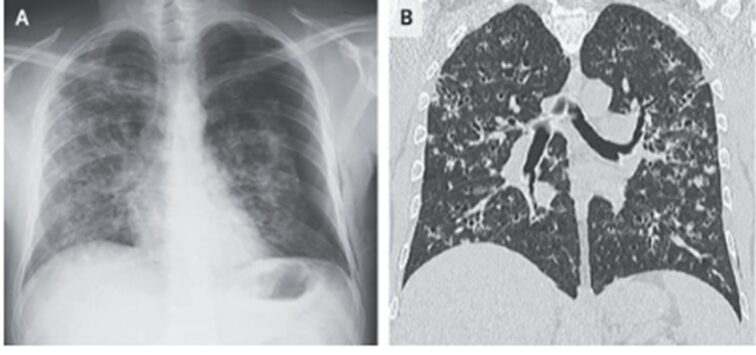

組織病理学的検査では、肺胞間中隔肥厚を伴うリンパ球性肺浸潤、好酸球、法膜状の細胞質および巨大核を有する大型細胞を認めた。

免疫組織化学染色ではS-100タンパク質、CD1a、胎盤酸性ホスファターゼ、ランゲリンが陽性だった。

「肺ランゲルハンス細胞組織球症」と診断された。